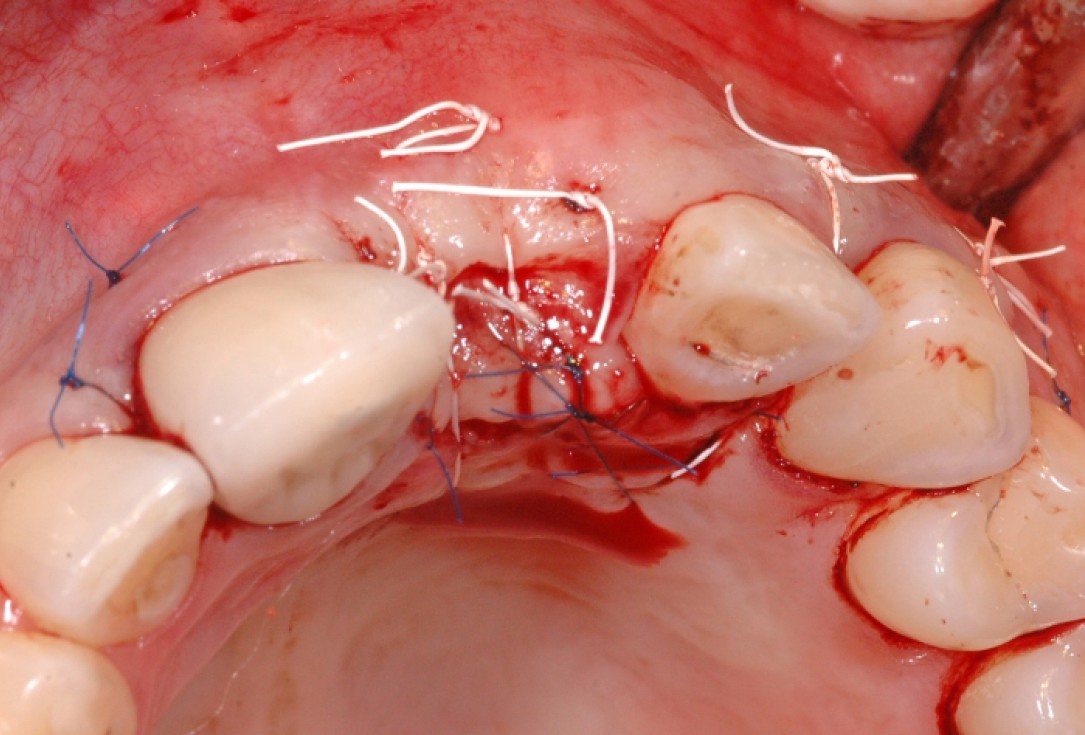

10/18 - Fixation of mucoderm® and suturing of the flapGBR together with soft tissue augmentation with mucoderm® and maxresorb® - Dr. S. Scherg